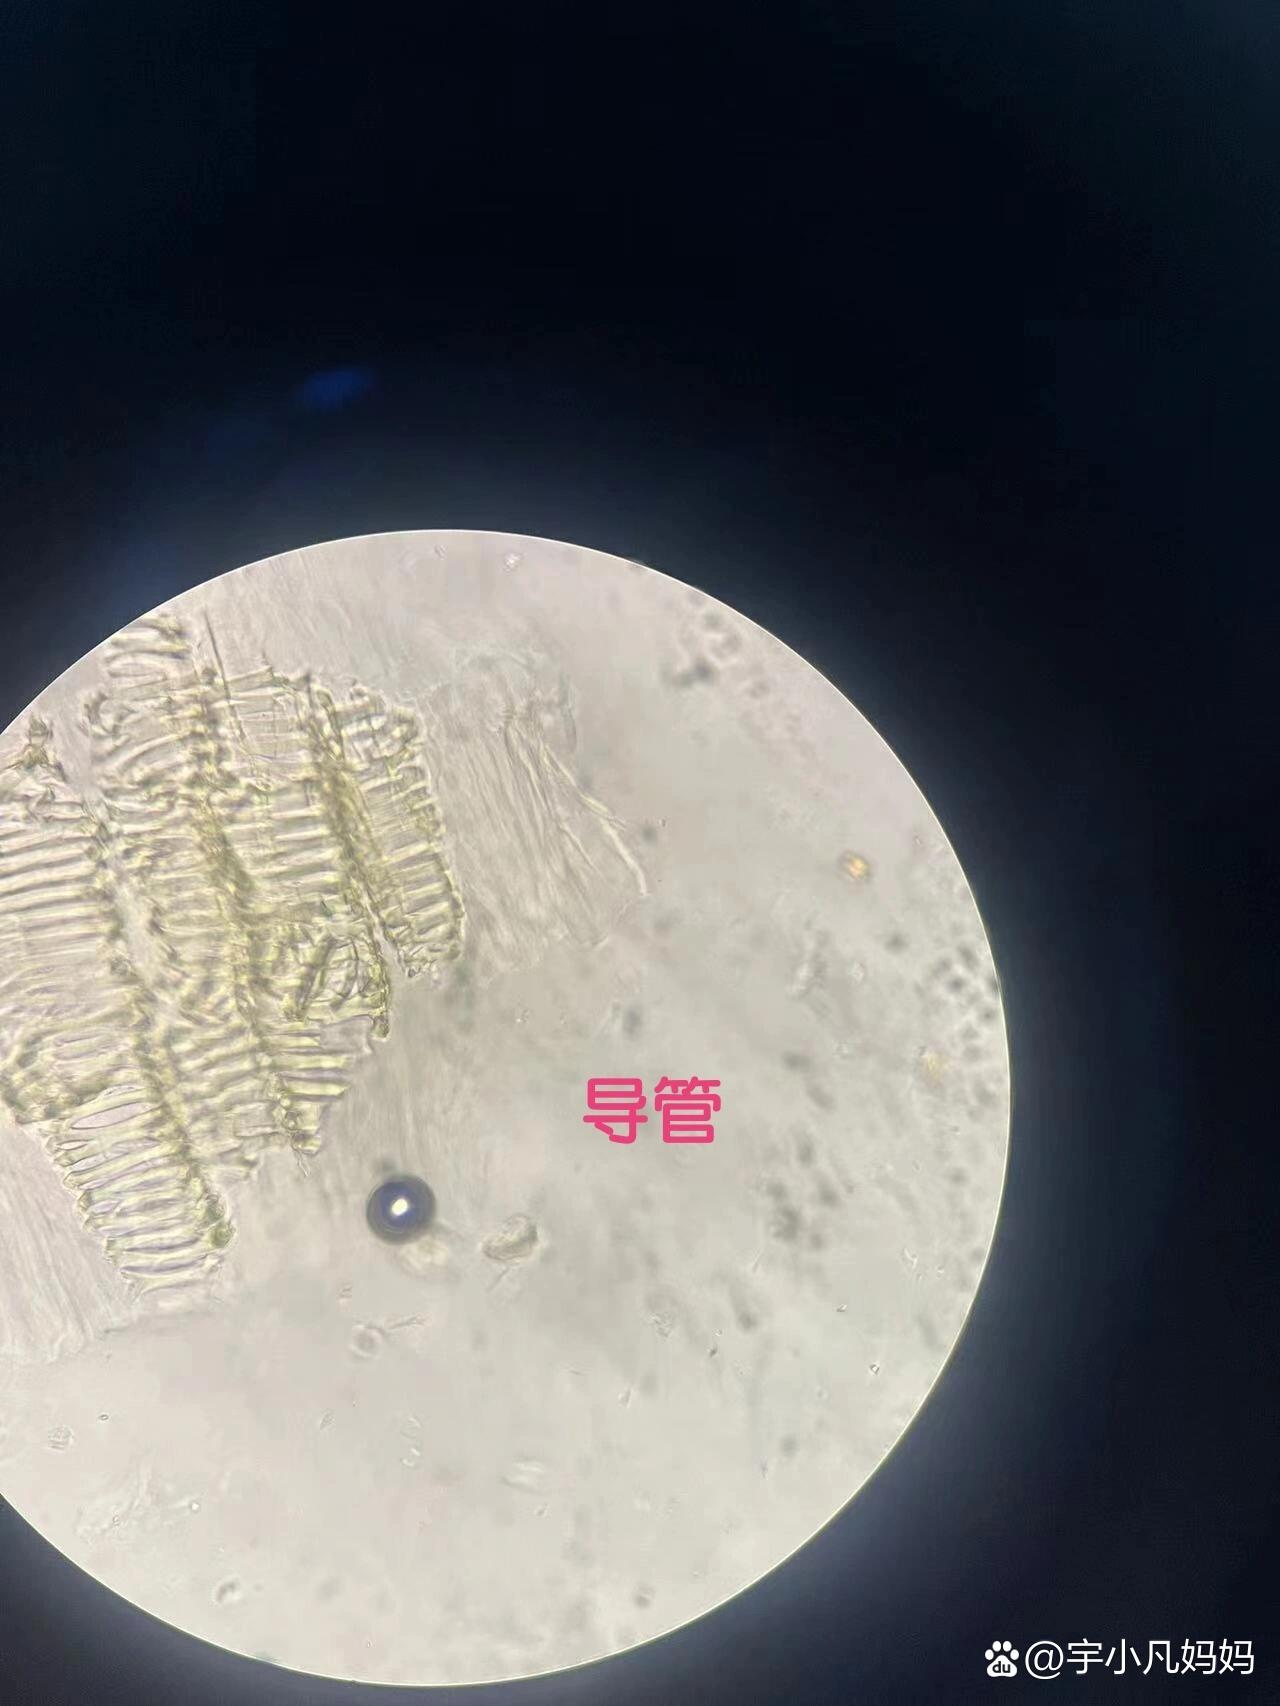

大黄药用大黄横切面显微特征图